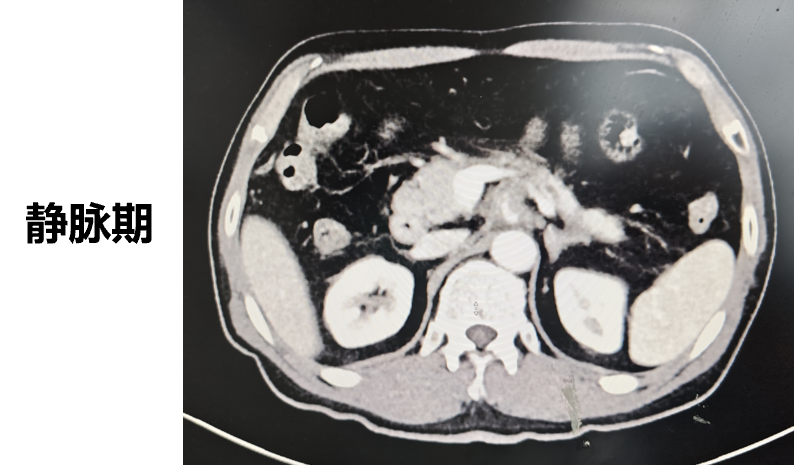

◈ 2023-3-9 上腹部MR增强扫描,对比2023-1-19上腹部MR:胰周多发囊性病变,考虑为术后改变(活检后),假性囊肿形成可能,较前吸收缩小;肠系膜上动脉、腹腔干近段及局部分支周围软组织影,较前缩小,研究者评估整体疗效为部分缓解(PR)。

2023-3-9上腹部MR增强扫描—TTFields联合化疗治疗五月余